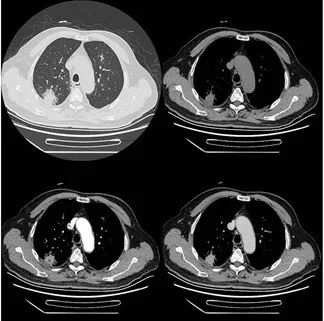

简单来说,CT平扫是最基础的CT检查,患者直接躺在机器里接受检查即可。而增强CT是在患者静脉内注射一定剂量的碘对比剂后进行CT检查。对比剂会让病灶和周围的血管、组织差异更明显,有助于发现平扫CT不能发现的病灶或者更清晰地显示病灶的范围和性质。拿胸部病变举例:平扫CT可以发现肺部阴影,但要明确性质,就需要进行增强CT检查。